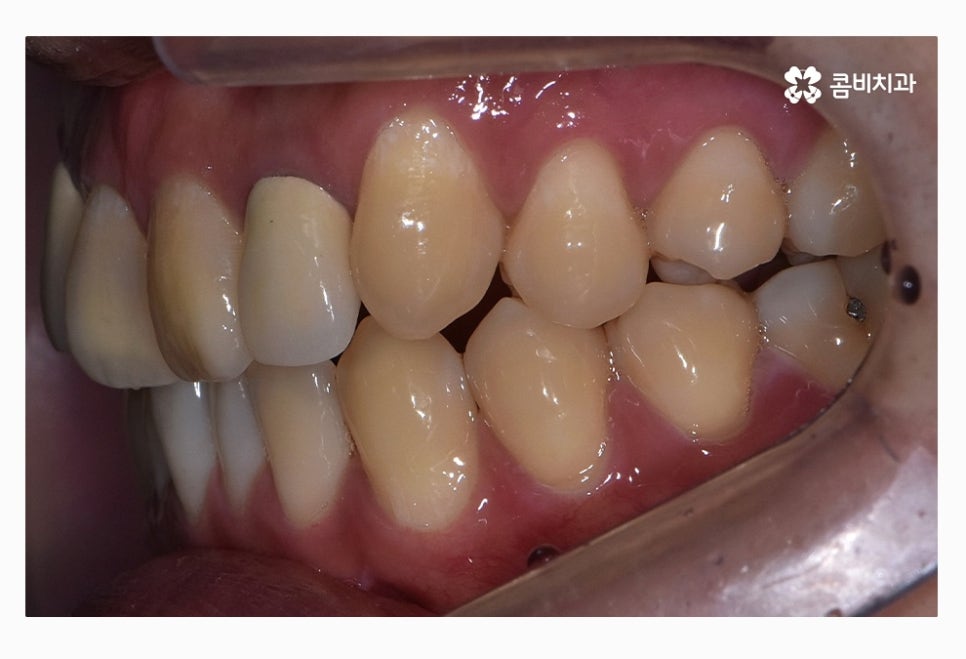

위 환자분의 경우 치열을 볼 때 정면에 비해서 측면으로 보면

앞니가 삐뚤어져 있는 것이 눈에 띄며 교합이 맞지 않아

윗니가 아랫니를 정상적으로 덮지 못하고 있는 상태이며

좌측 사진이 윗니이며 우측 사진이 아랫니인데

윗니가 치열이 좀 더 삐뚤다는 것을 알 수 있어요.